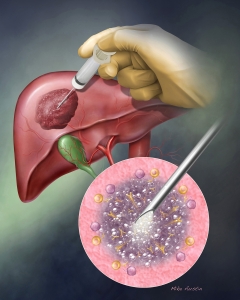

Internal Art Medical Illustration

Blending Art, Anatomy and Science for Creative Visuals

Patient & Professional Marketing

Welcome to my Patient and Professional Marketing page, where I harness the power of anatomical illustrations to educate and empower both patients and medical professionals. My unique approach combines artistry and education to convey complex surgical procedures and the utilization of medical devices in an easily understandable manner.